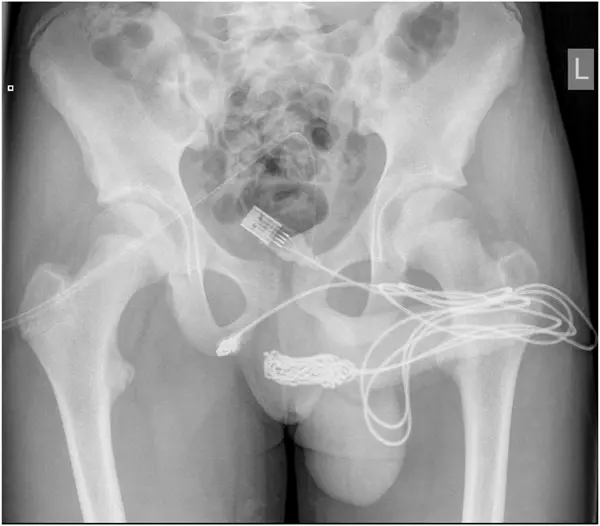

วันที่ 17 กันยายน 2564 สำนักข่าวต่างประเทศ รายงานว่า เด็กหนุ่มชาวอังกฤษวัย 15 ปี ที่ขี้สงสัยของเขาทำให้ต้องลำบากถึงคุณหมอ หลังจากที่เขาสอดสาย USB เข้าไปในอวัยวะเพศของตัวเอง เรื่องนี้ถูกเปิดเผยใน Urology Case Reports ซึ่งเป็นวารสารการแพทย์ โดยเด็กชายนำสาย USB เข้าไปในอวัยวะเพศ ซึ่งได้นำส่วนที่เป็นก้อนปมยัดเข้าไปทางรูอวัยวะเพศจนเกิดการอักเสบและฉี่เป็นเลือด

เนื่องจากสายเข้าไปติดอยู่ภายในท่อปัสสาวะ โดยมีส่วนหัว USB ทั้ง2 ฝั่ง ห้อยออกมาภายนอก ซึ่งเด็กหนุ่มได้พยายามจะดึงออกเองอยู่หลายครั้งแต่ก็ไม่สำเร็จ จนในที่สุดทางครอบครัวก็ช่วยกันนำตัวเขาส่งไปยังโรงพยาบาลท้องถิ่นแต่ ทางโรงพยาบาลไม่สามารถทำการรักษาได้เนื่องจากการกระทำดังกล่าวส่งผลทำให้เกิดภาวะโลหิตจาง จึงส่งตัวเด็กหนุ่ม ไปยัง University College Hospital London เพื่อทำการผ่าตัดด่วน